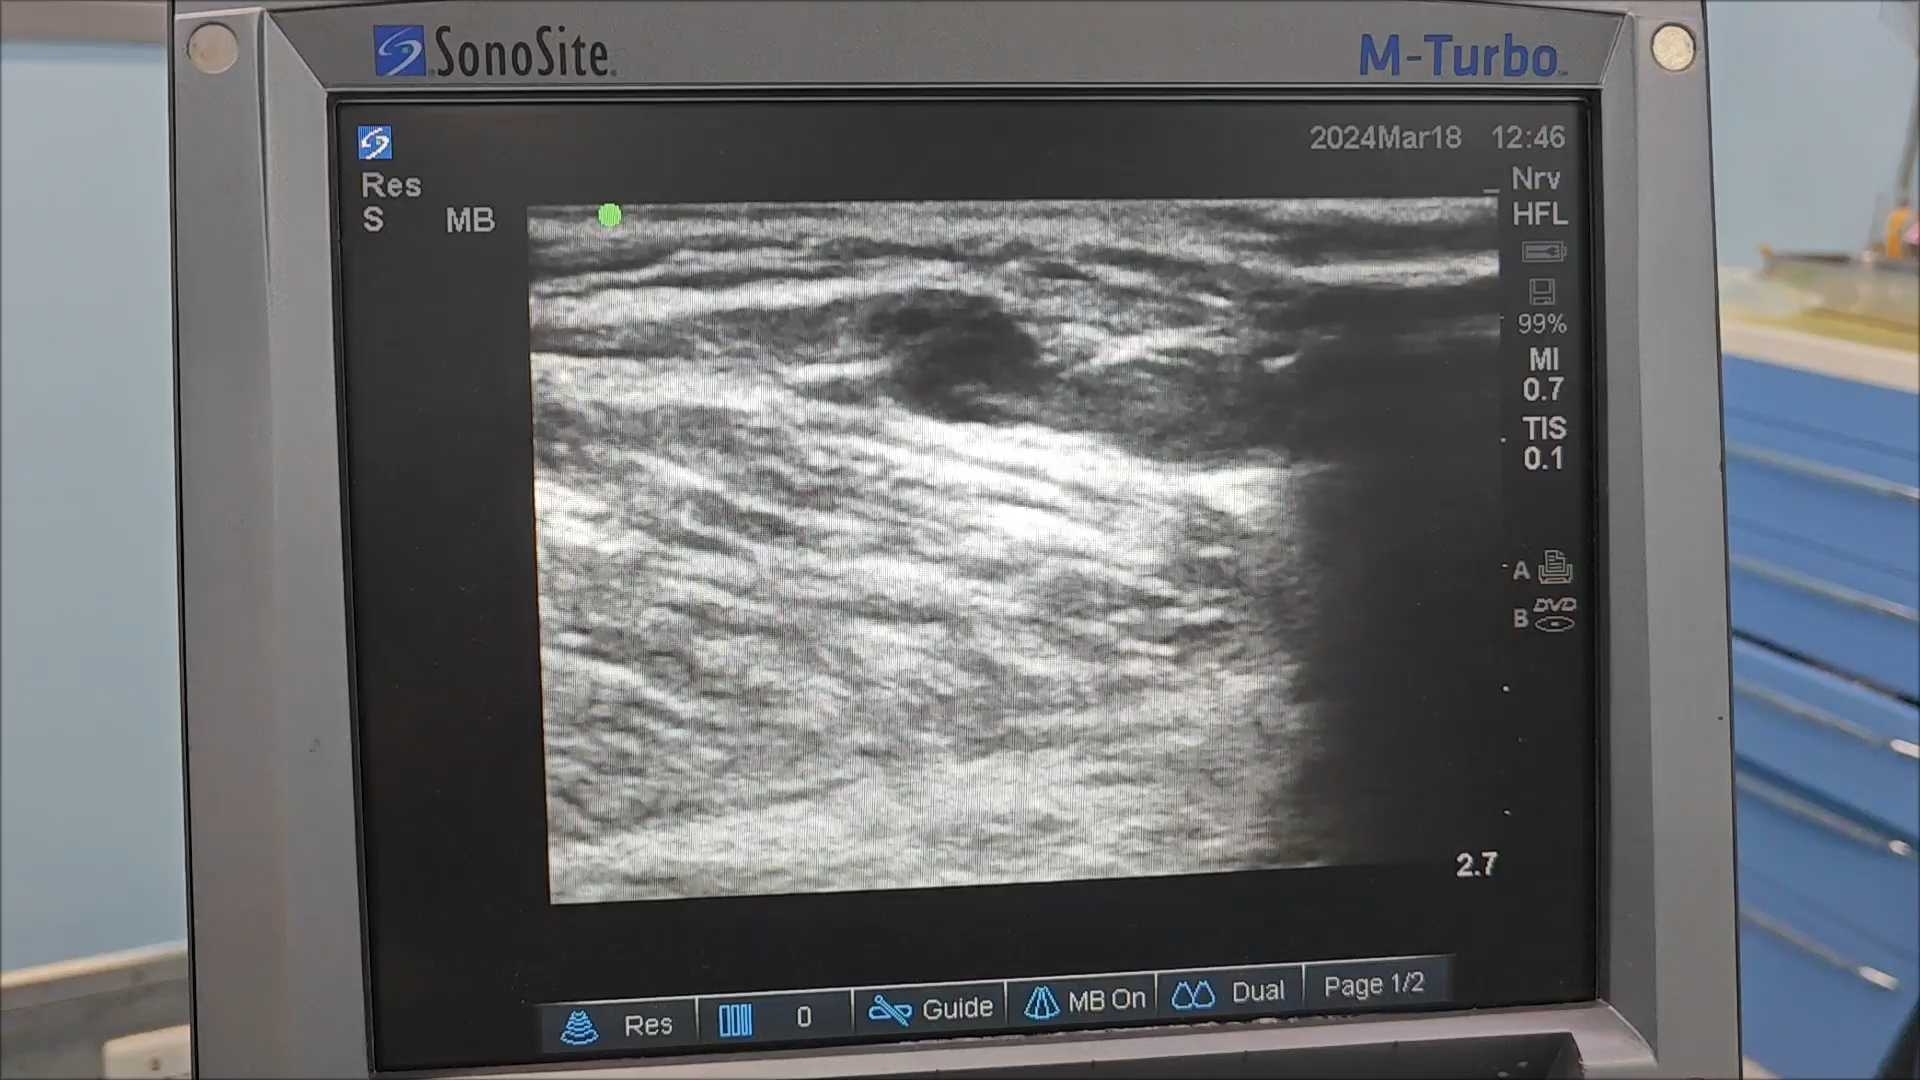

超声评估显示,大隐静脉全程扩张,直径达11mm,反流时间长达4秒,推测原手术可能仅结扎了分支,或未寻及并成功实施高位结扎。因此,我们再次为其进行了左下肢大隐静脉高位结扎剥脱术。

去年9月,一位65岁女性患者因“右下肢浅静脉扩张迂曲20年”入院。初看以为是常规大隐静脉曲张,但超声评估发现,大隐静脉上段管径正常,中段却存在一条直径4mm的病理性穿通静脉反流,导致其下方大隐静脉及属支扩张迂曲。